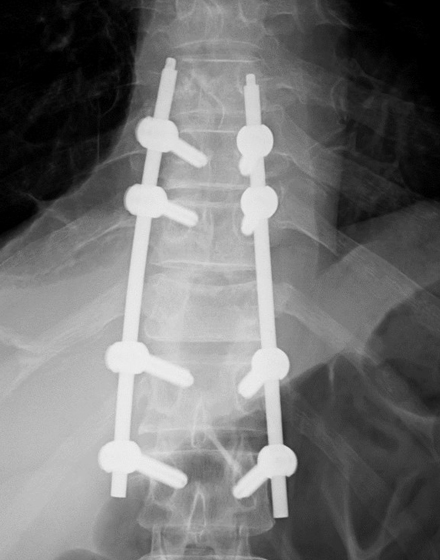

最小侵襲脊椎安定術 MISt(ミスト)

適応となる疾患:転移性脊椎腫瘍、化膿性脊椎炎、脊椎骨折など

がんの脊椎転移、脊椎の細菌感染、外傷による脊椎骨折など脊椎の安定性が失われた病態に対して行われる低侵襲な手術です。脊椎に挿入する金属スクリューを、経皮的に刺入するために皮膚切開が小さく、筋肉に対するダメージを最小限にすることができます。出血量も低減させ、早期離床、早期リハビリが可能な手術です。術後の安静期間や入院期間は病態に応じて異なります。